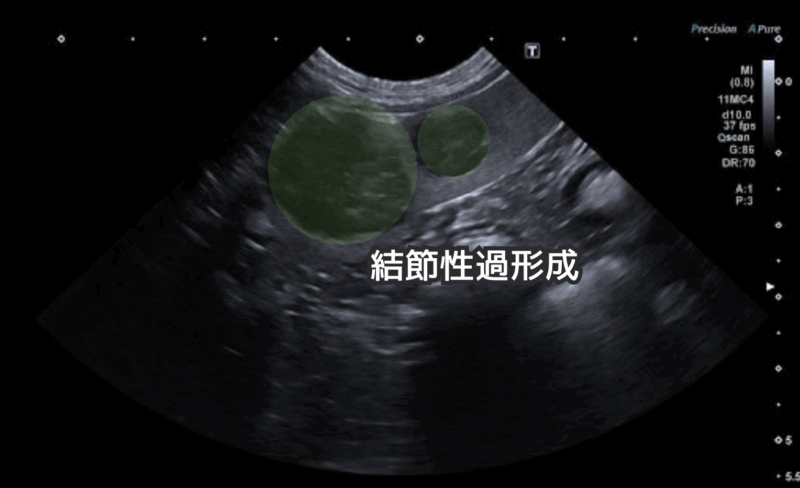

腰の痛みで当院を受診し、エコー検査を行ったところ、偶発的に脾臓に2つの腫瘤が見つかりました。

こちらが脾臓の腫瘤のエコー画像です。

脾臓を摘出し、病理検査に出しました。

病理検査の結果は結節性過形成で、良性の腫瘍でした。